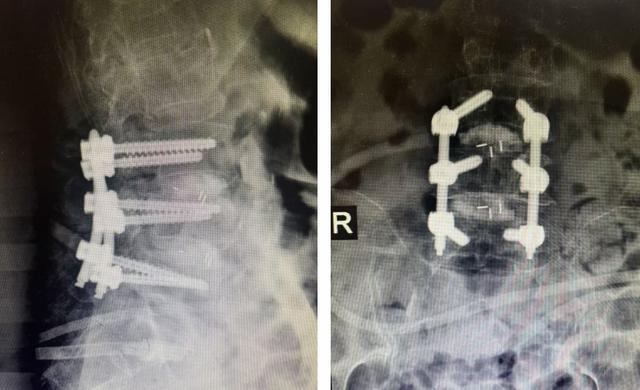

手术在全麻下进行,团队通过两个微小切口建立通道

在高清内镜下,彻底松解被压迫的神经根。

精细处理椎间隙,植入融合器,为骨骼愈合创造条件。

在影像引导下,精准置入螺钉,完成脊柱复位与固定。

整个手术历时3小时,出血量仅约40毫升。当宋奶奶在麻醉复苏后,第一时间感受到腰腿痛明显减轻时,所有医护人员都倍感欣慰。